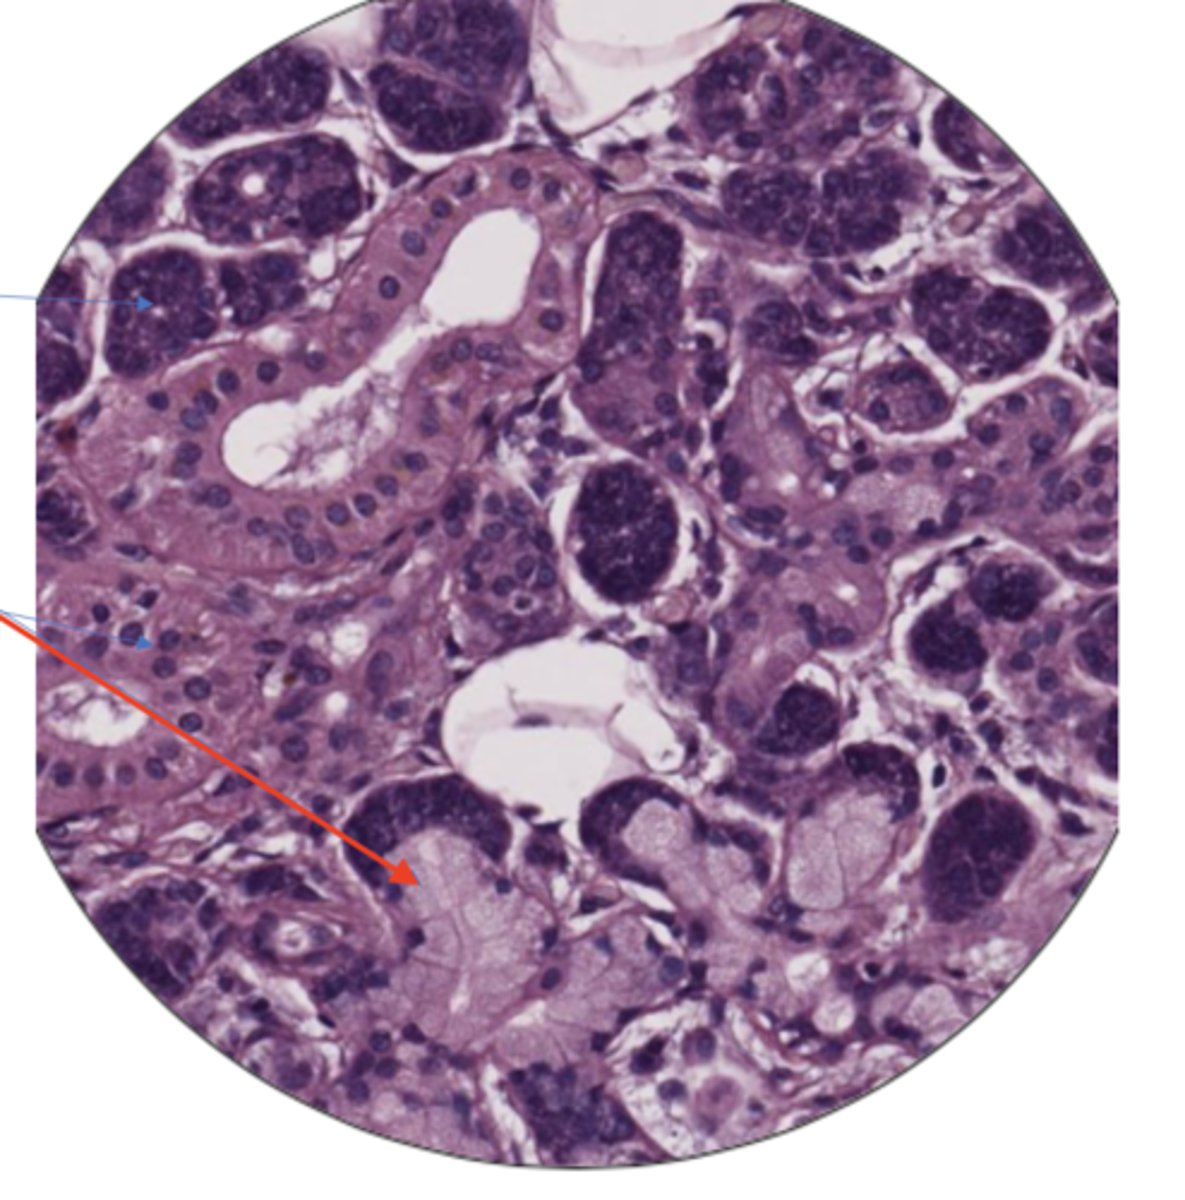

seminiferous tubule

leydig cells

sperm cell

sperm mass